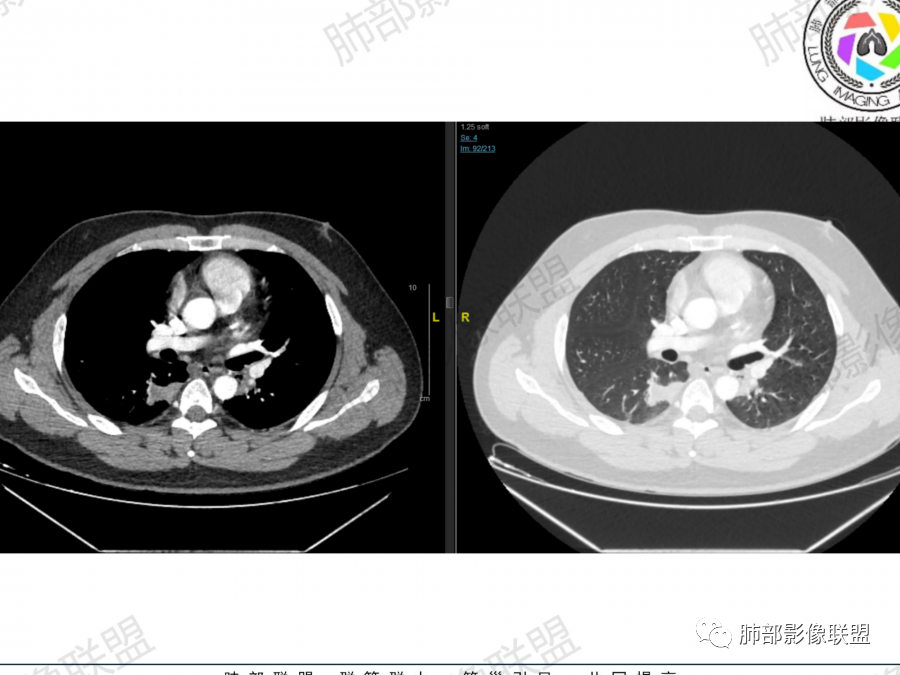

主要征象:右肺多发病变  一元论?二元论?

1.右上肺团块:分叶,不均性强化,其内支气管走行自然,增强血管影可见、清晰。

疑问:空洞还是残余肺组织?

2.右下肺结节、实变:胸膜下,长轴平行胸膜。部分似有晕影。支气管进入后近段截断